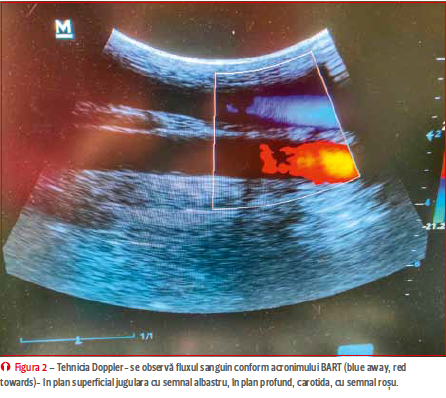

Ultrasonografia este o tehnică non invazivă, simplă și valoroasă în evaluarea magnitudinii formării trombusului sau chiar a unei potențiale tromboflebite septice, care este greu de diferențiat clinic. Ea oferă imagini în timp real a structurilor anatomice implicate și permite clinicianului să ia decizii clinice juste pentru pacientul în cauză, întrucât modificările peretelui vascular sunt evidente inițial doar la nivel local și nu sunt clinic manifeste decât mai târziu (chiar și cu 24 de ore), fiind necesare examinări seriate. Astfel, ultrasonografia permite evaluarea pereților vasculari, a gradului

de compromitere a fluxului sanguin la nivel local inclusiv prin intermediul tehnicii Doppler (figura 2), prezența, dimensiunea și forma unui eventual trombus precum și, la cazurile cronice, prezența vascularizației vicariante sau a recanalizării. Pentru o examinare

iar dimensiunea si extensia sa la nivelul structurilor anatomice adiacente pot fi urmărite cel mai bine cu ajutorul secțiunii longitudinale. Se poate utiliza ecografia Doppler (pulsed wave sau color flow) pentru a pune în evidență fluxul sanguin

(figura 2);